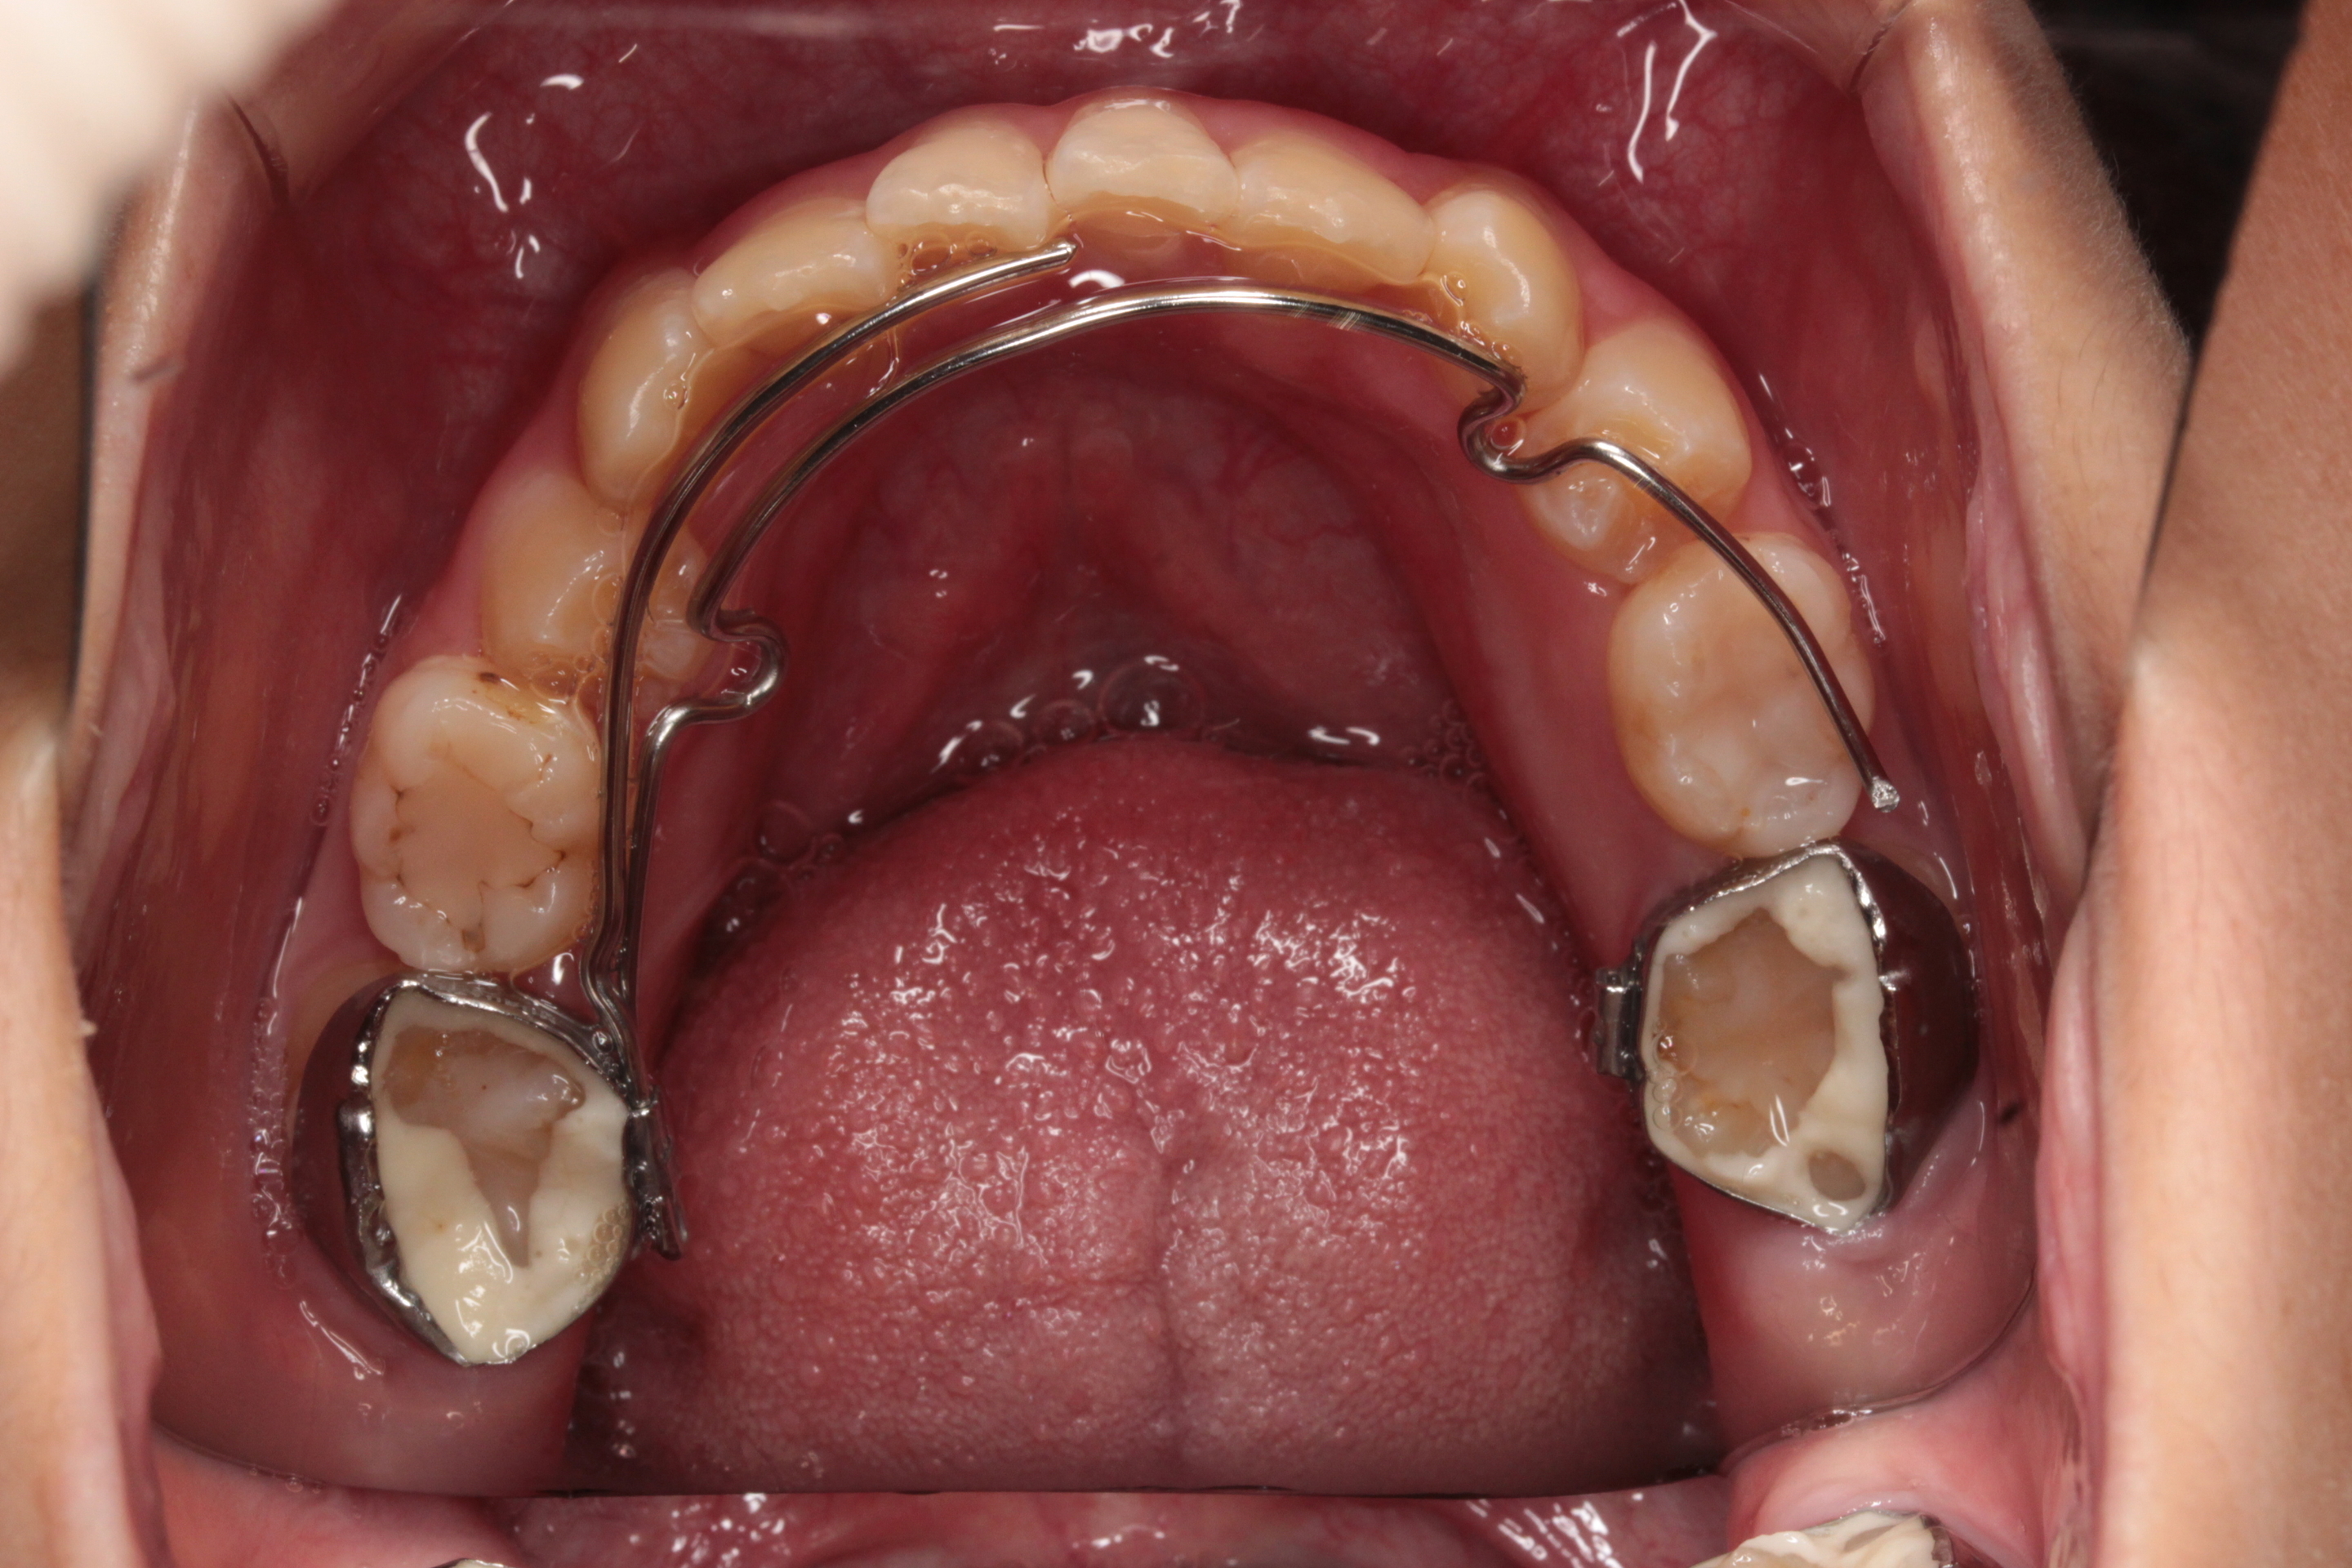

TPAの取り扱いについて

TPA

※取り外しの出来ない装置です!

- 目的

上あごの保定。後戻りを防止する装置です。

- 使用方法

ご自宅で何かしていただくことはありません。

1ヶ月に一度来院時に先生が調整します。

- 変化

装着してから1週間くらいは噛む時に奥歯(バンドがついている歯)が痛んだり、ワイヤーによって歯が押される感じがします。慣れるまで様子をみてください。

- 注意事項

ワイヤーと接している歯は汚れがのこりやすいので、しっかり歯磨きをしてください。

慣れるまで違和感がありますが、舌で必要以上にさわったり、指で触ったりしないようにしましょう。

- 緊急事態

接着剤がはがれてバンドが外れてしまったり、ワイヤーの先が歯茎に食い込んでしまった場合にはなるべく早く連絡し来院いただきますようお願いします。

また、ワイヤーが変な方向へ曲がってしまった場合も、早めに連絡をして来院ください。

痛みについては、装着後1週間ほどは様子をみてください。痛みが続くようでしたらご相談ください。